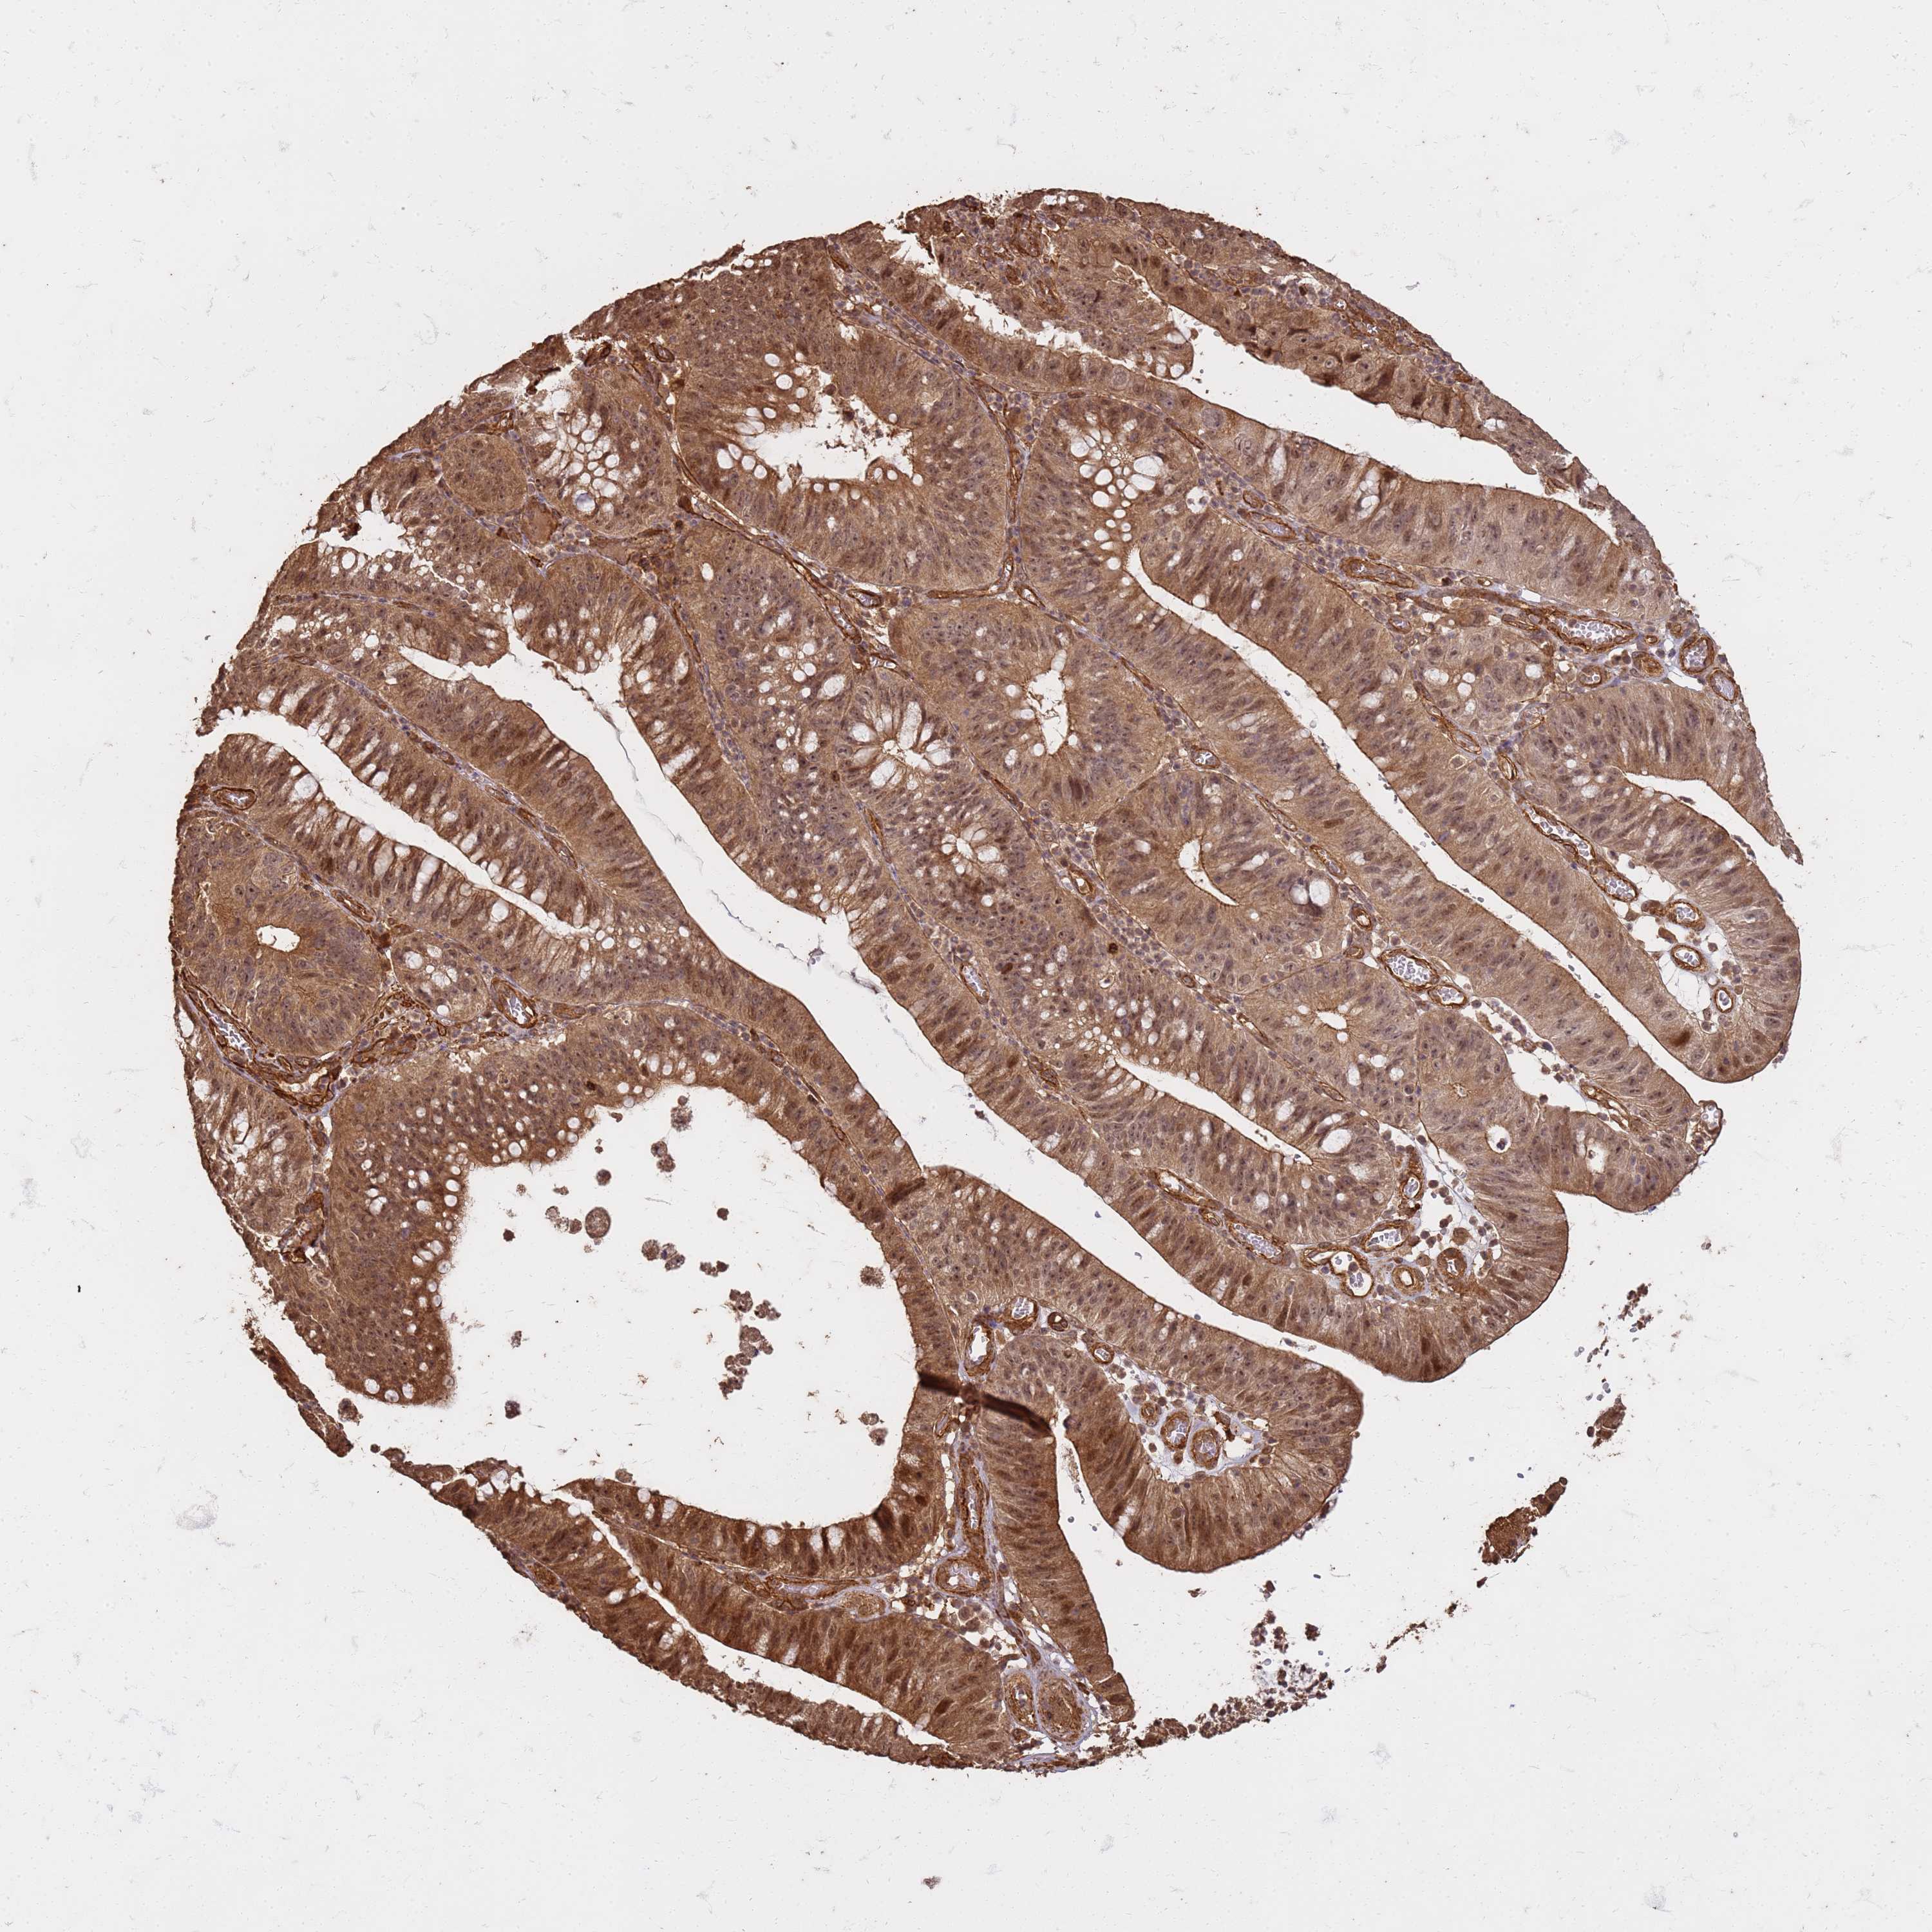

STOMACH CANCER - Protein expressioni

A mouse-over function shows sample information and annotation data. Click on an image to view it in a full screen mode. Samples can be filtered based on level of antibody staining by selecting one or several of the following categories: high, medium, low and not detected. The assay and annotation is described here.

Antibody stainingi

Antibody staining in the annotated cell types in the current human tissue is reported as not detected, low, medium, or high, based on conventional immunohistochemistry profiling in selected tissues. This score is based on the combination of the staining intensity and fraction of stained cells.

Each image is clickable and will lead to virtual microscopy that enables deeper exploration of all samples and also displays staining intensity scores, fraction scores and subcellular localization as well as patient and tissue information for each sample.

Antibody HPA046882

Antibody HPA060346

Staining

High

Medium

Low

Not detected

Intensity

Strong

Moderate

Weak

Negative

Quantity

>75%

75%-25%

<25%

None

Location

Nuclear

Cytoplasmic/membranous

Cytoplasmic/membranous,nuclear

Adenocarcinoma, NOS

Adenocarcinoma, High grade